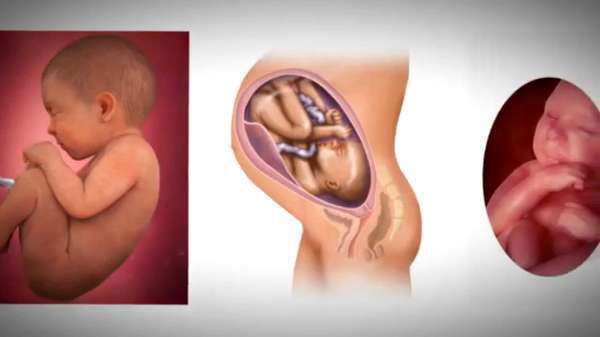

Этапы беременности: иллюстрации и развитие

Раздел: Лаборатория идей